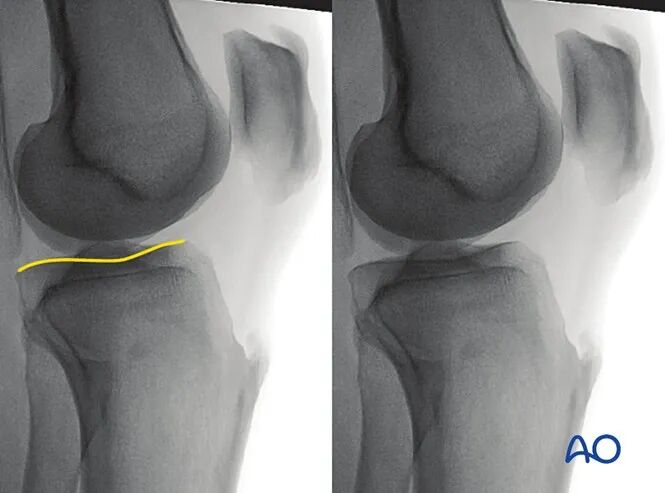

5. 评估外侧胫骨平台的改良侧位

最佳体位摆放要求

以标准侧位为基础体位,

将患侧下肢外展约10°-20°。

最佳影像的验证标准

满足以下条件即为评估外侧胫骨平台的最佳改良侧位影像:

●外侧胫骨平台的凸面轮廓在关节间隙内清晰显示,且位于内侧胫骨平台凹面的头侧;

●外侧胫骨平台居中显示于影像屏幕。

可识别的解剖标志与线条

该体位下可识别的解剖标志与线条为:

外侧胫骨平台。

临床观察要点

该体位尤其适用于判断以下情况:

●关节面不平整;

●植入物穿入关节腔。

6. 评估内侧胫骨平台的改良侧位

将患侧下肢内收约10°-20°。

满足以下条件即为评估内侧胫骨平台的最佳改良侧位影像:

●内侧胫骨平台的凹面轮廓在关节间隙内清晰显示,且位于外侧胫骨平台凸面的头侧;

●内侧胫骨平台居中显示于影像屏幕。

内侧胫骨平台。